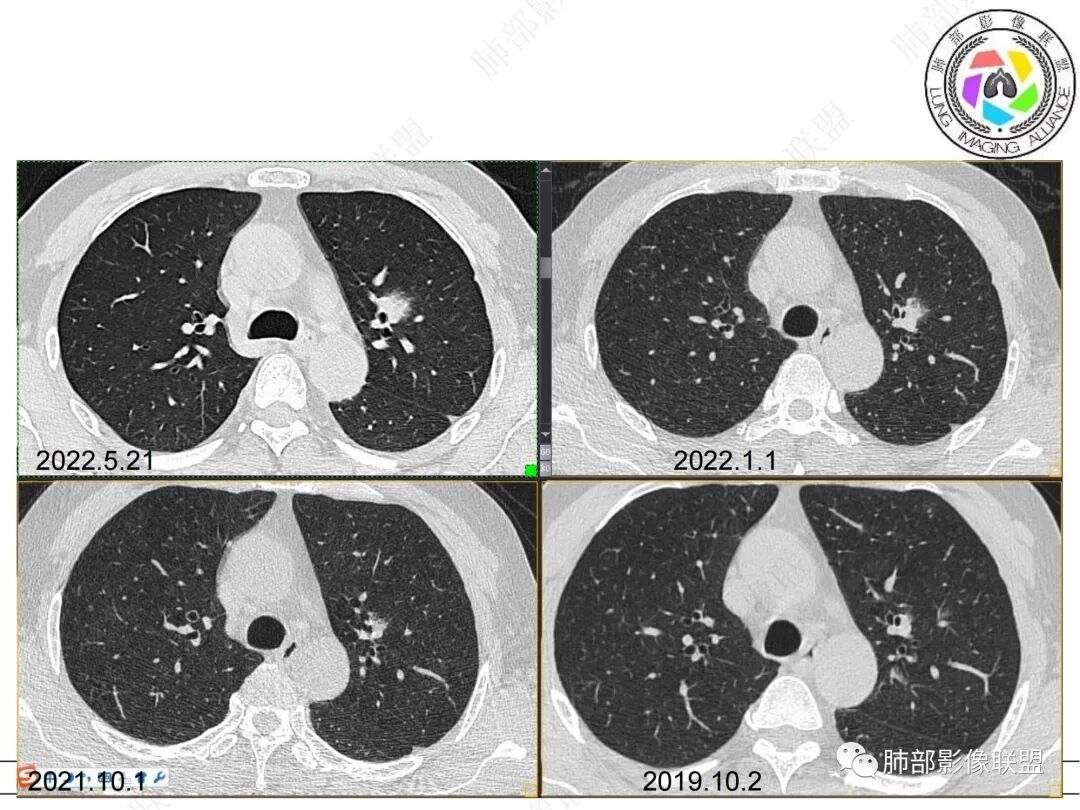

57岁,属于高危人士;病灶3年逐步增大,肿瘤按理是要考虑的

初始病灶应该是这里

病灶朝前、外侧进展

1、临床:57岁男性,3年逐步增大。孤立病灶持续三年原地坐大,符合肿瘤性病变,恶性程度不高或者早期进展缓慢。良性肿瘤常多年静止或进展极其缓慢。炎性病灶“星火”可以燎原,临床表现也会逐步加重。尽管继发性肺结核可以相对惰性,但病灶强化不明显,多结节、多卫星、多新旧不等,相对清楚硬朗。

2、病灶以实性密度为主,前、外侧蔓延,GGO部分边界清楚,部分欠清

1、连续3年观察,病灶逐步增大,符合惰性恶性肿瘤。2、支气管壁增厚,腔内内壁无变化——病灶长轴沿支气管周围蔓延;朝外走,内侧没有,提示病灶间质为主,与支气管无关。